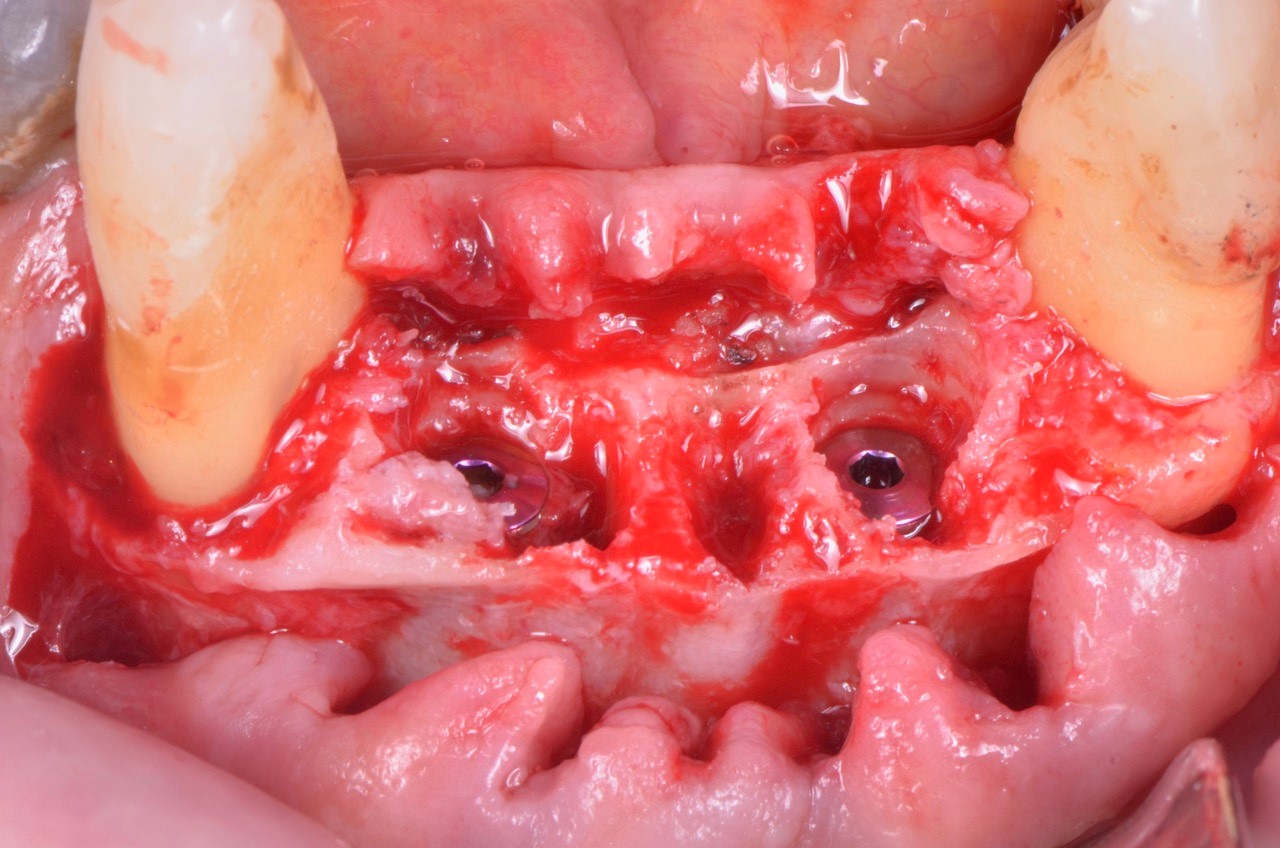

Foto: Posizionamento subcrestale di due impianti MIS V3